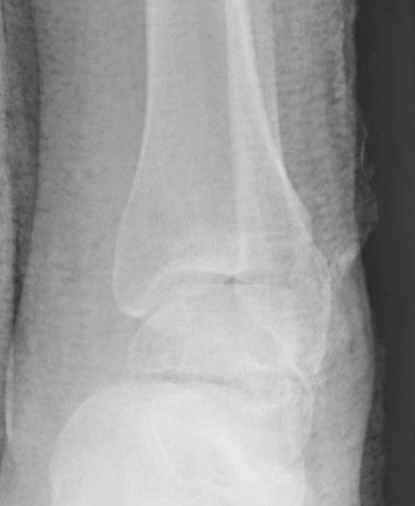

Уважаемые участники русского Ортофорума, поздравляю всех со всеми прошедшими праздниками: Новым годом, Рождеством, Hanukkah, Kwanzaa, желаю участникам всего наилучшего и здоровья.Повреждение таранной кости.Больной 81г автоавария, повреждение таранной кости, здесь снимки. Какие рекомендации?Djoldas Kuldjanov, MDDepartment of Orthopedic SurgerySt. Louis University Medical Center

Вдогонку по поводу перелома таранной кости, больная 81, не страдает диабетом, перелом закрытый, в первый же день поступления ограничились временным наружным фиксатором (как на снимке).

Планировалась открытая фиксация после спадения отека, но больная пожелала лечиться по месту жительству в другом штате..